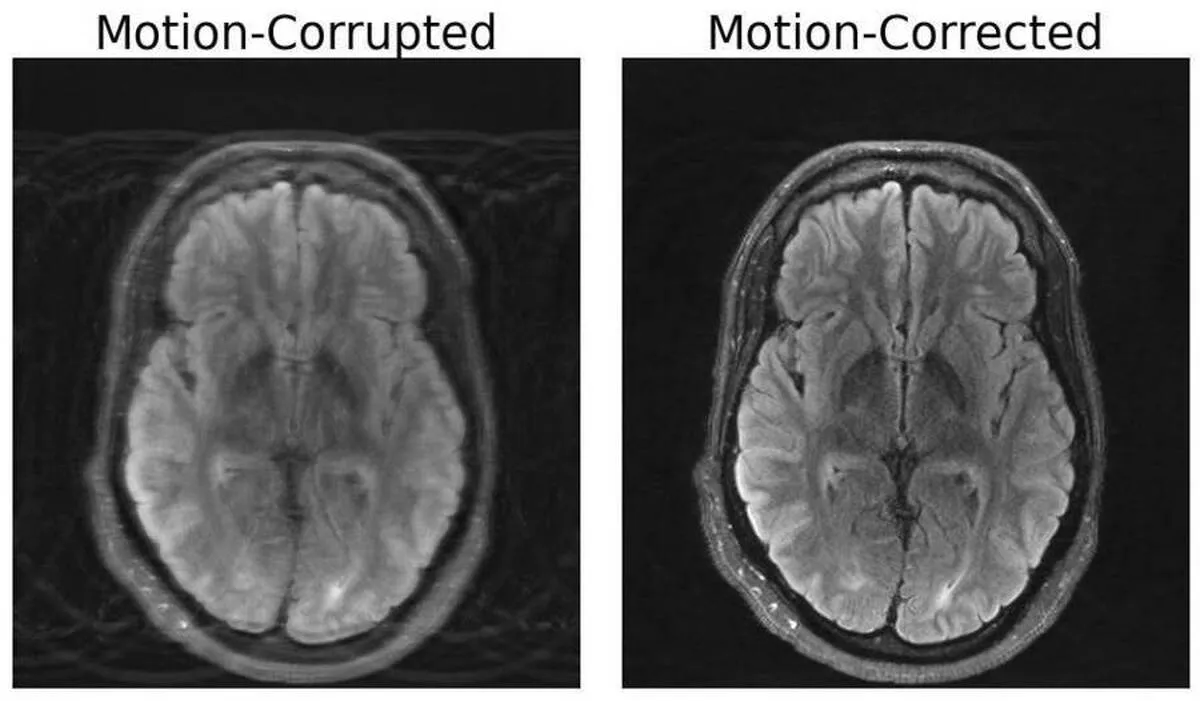

Compared to other imaging modalities like X-rays or CT scans, MRI scans provide high-quality soft tissue contrast. Unfortunately, MRI is highly sensitive to motion, with even the smallest of movements resulting in image artifacts. These artifacts put patients at risk of misdiagnoses or inappropriate treatment when critical details are obscured from the physician. But researchers at MIT may have developed a deep learning model capable of motion correction in brain MRI.

The paper, titled “Data Consistent Deep Rigid MRI Motion Correction,” was recently awarded best oral presentation at the Medical Imaging with Deep Learning conference (MIDL) in Nashville, Tennessee. The method computationally constructs a motion-free image from motion-corrupted data without changing anything about the scanning procedure. “Our aim was to combine physics-based modeling and deep learning to get the best of both worlds,” Singh says.